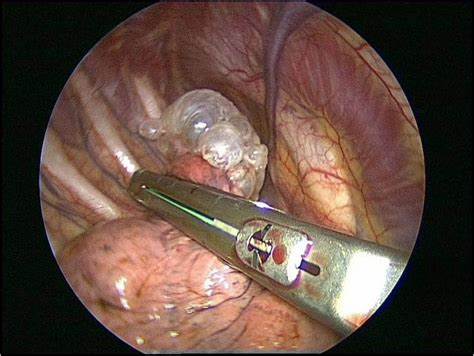

- 흉관삽입술

- 화학적 흉막 유착술(테트라사이클린, 활석가루)

- 수술(소기포절제)